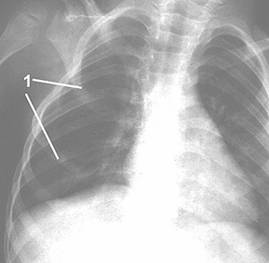

Рис. 1. Фото и рентгенограмма грудной клетки больной С. 4 лет с синдромом Поланда справа.

1 - гипоплазия 3 и 4 ребер справа.